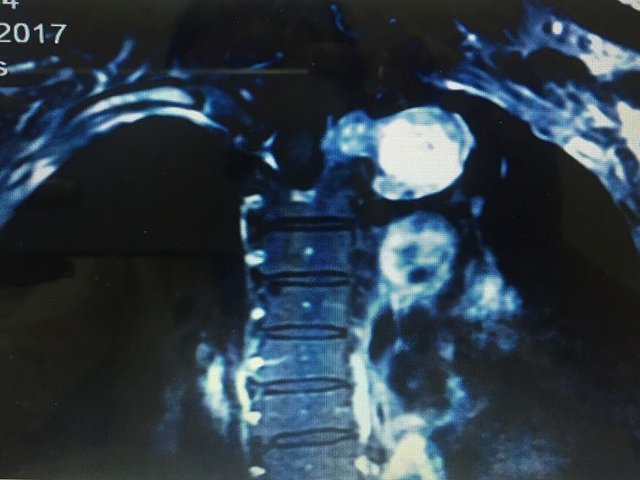

Khối u khổng lồ hình quả tạ ở lồng ngực người phụ nữ

<strong>Bị tức ngực, đau lưng, nữ bệnh nhân 61 tuổi (Quảng Ninh) đến viện khám phát hiện khối u lớn ở tủy sống, lồng ngực.</strong><br />